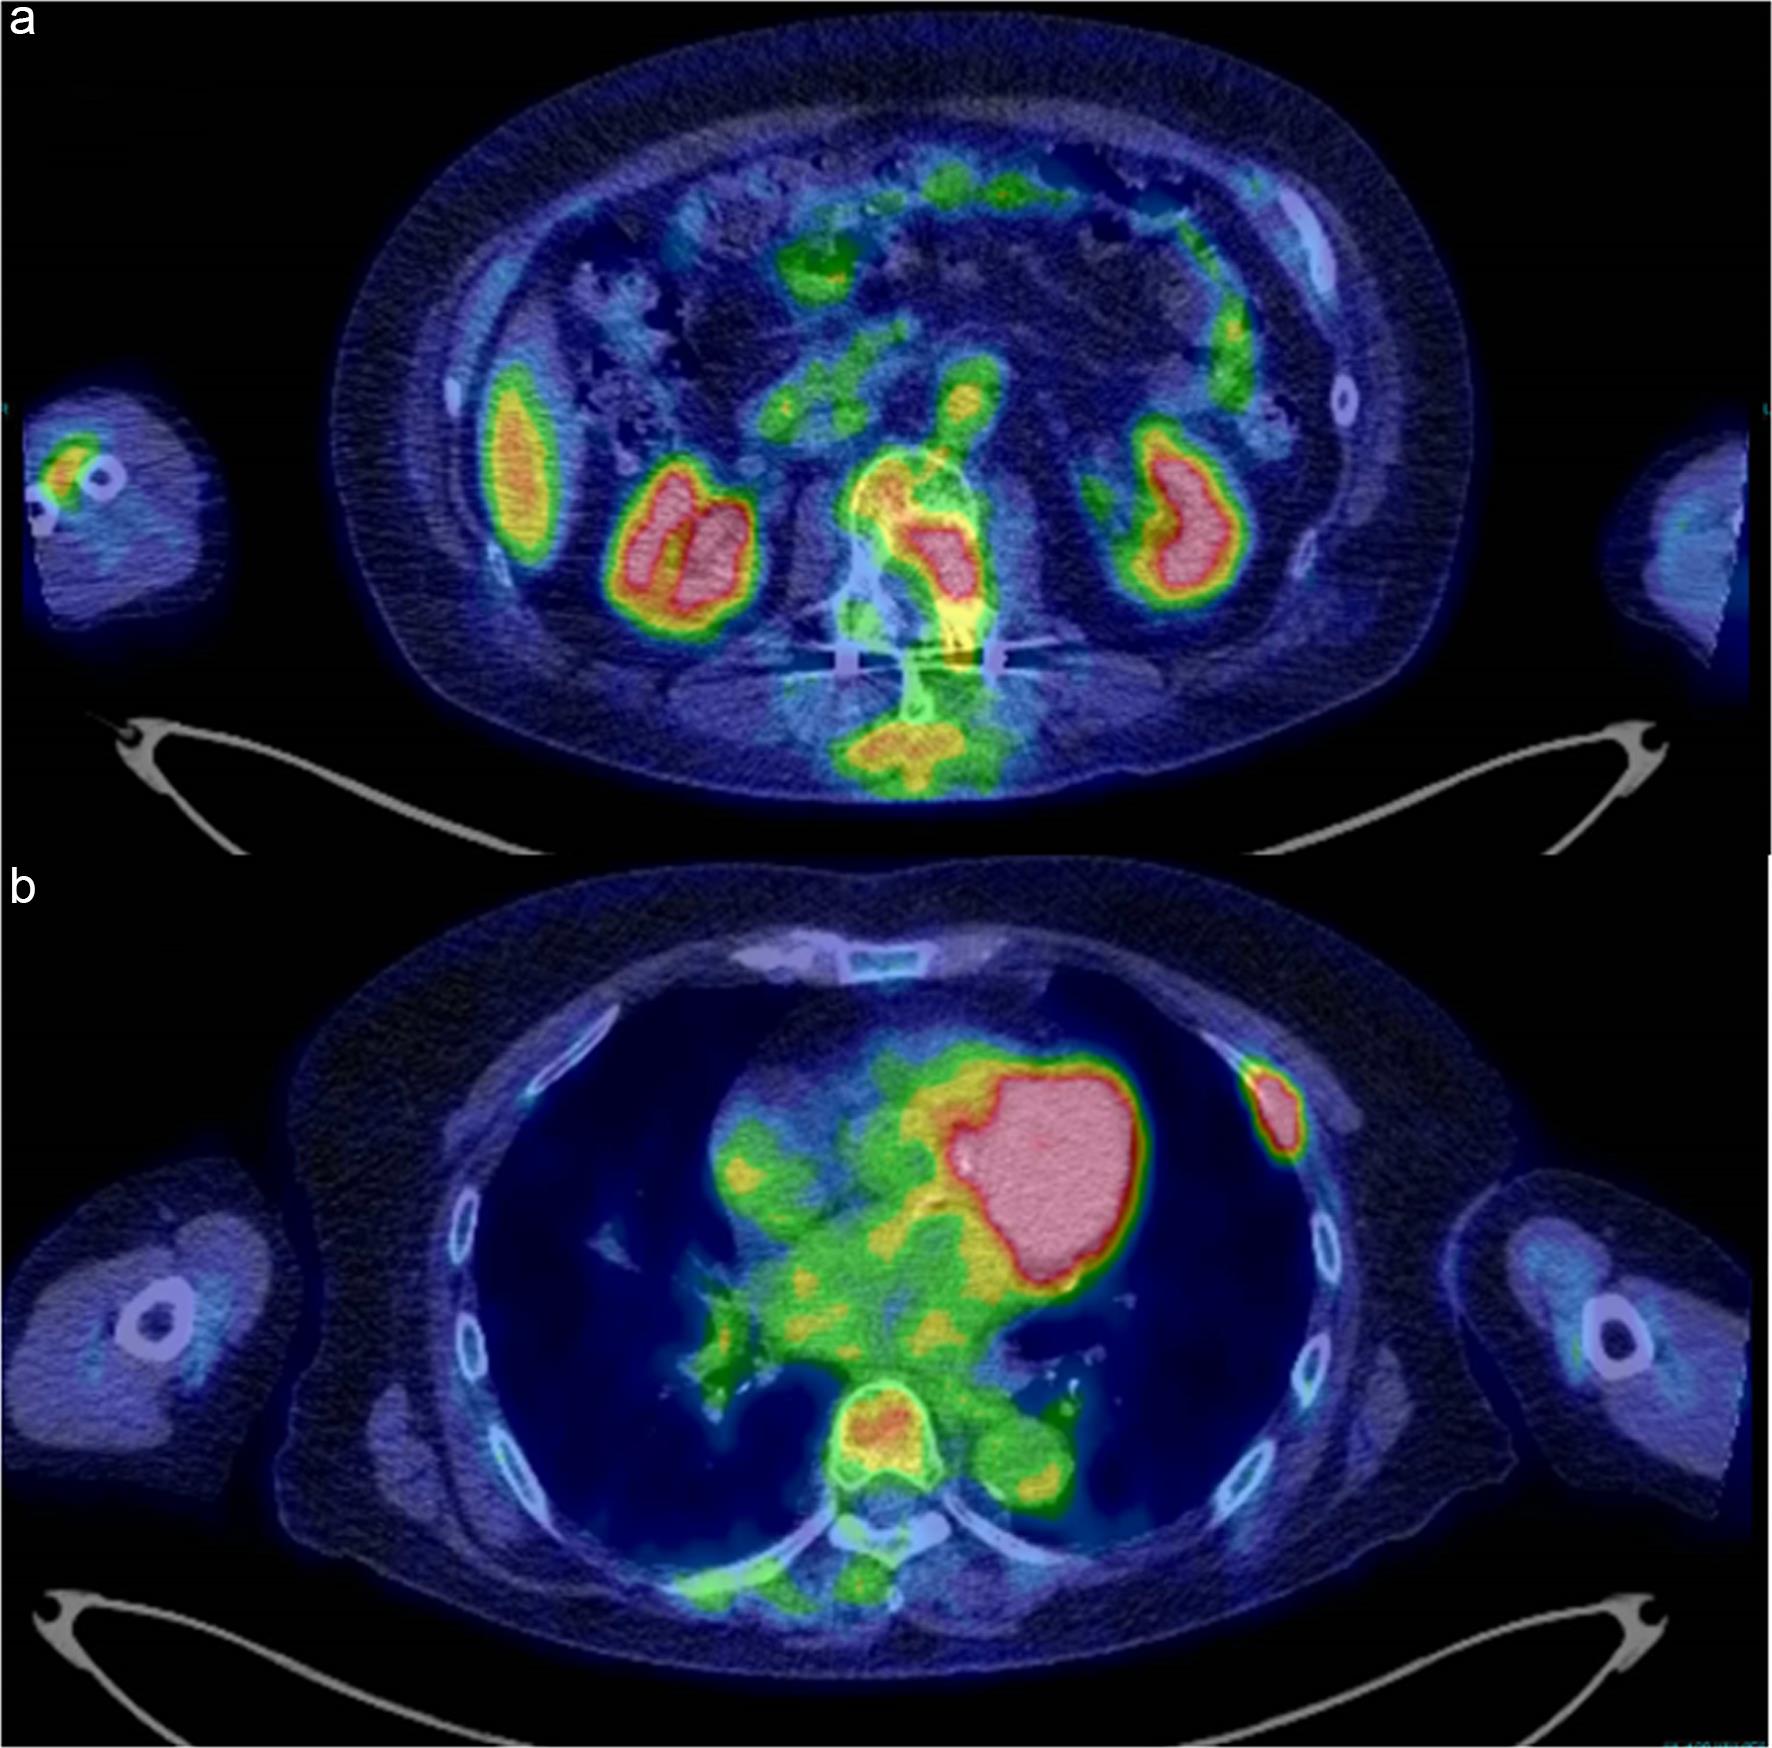

After receiving two courses of modified CHOP (cyclophosphamide 10 mg/kg, day 1; doxorubicin 35 mg/m2, day 1; vincristine 0.05 mg/kg, day 1; prednisolone 30 mg/day, days 1–5) q4 weeks for the mixed LCH/ECD relapse,14 PET/CT revealed a poor response, with persistence of the L2 lesion (Fig. 3a) and emergence of new lesions in the left 6th rib (Fig. 3b) and the proximal metaphysis of the left femur (data not shown). In addition, the patient achieved only a partial response after five courses of cladribine (0.09 mg/kg, days 1–5) q4 weeks, prompting a switch to reduced doses of targeted therapy with daily oral dabrafenib (50 mg/day) and trametinib (1 mg/day) due to cladribine-induced myelosuppression. Ultimately, all fluorodeoxyglucose-avid lesions disappeared on PET/CT following targeted therapy. Continuation of dabrafenib/trametinib with an increase in doses is planned to maintain remission, given reports of disease recurrence upon interruption of targeted therapy.15,16

PET/CT images of the refractory histiocytic lesions after chemotherapy with the CHOP regimen.

Fig. 3  PET/CT images of the refractory histiocytic lesions after chemotherapy with the CHOP regimen.

FDG-avid signals persisted at the L2 vertebral body and the left vertebral arch (SUVmax = 5.4) (a). In addition, newly developed signals at the left rib (SUVmax = 18.6) (b) and at the proximal metaphysis of the left femur (SUVmax = 3.8) (data not shown) were noted. CHOP, cyclophosphamide, doxorubicin, vincristine, prednisolone; CT, computed tomography; FDG, fluorodeoxyglucose; PET, positron emission tomography; SUVmax, standardized uptake value (maximum).